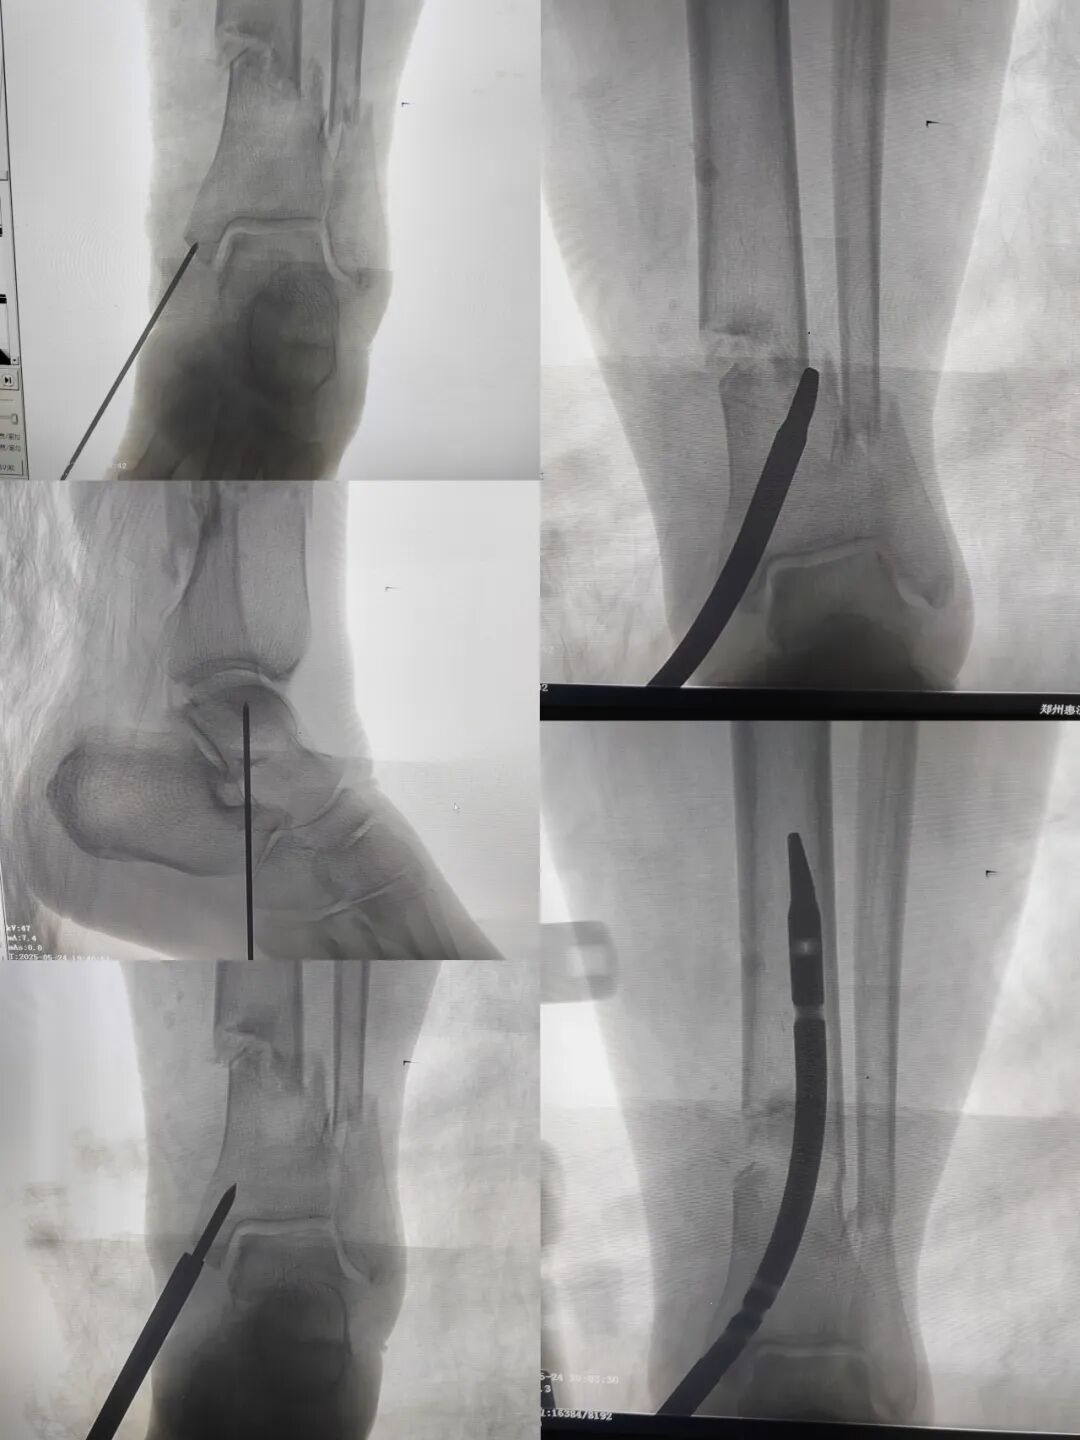

图片

术后影像